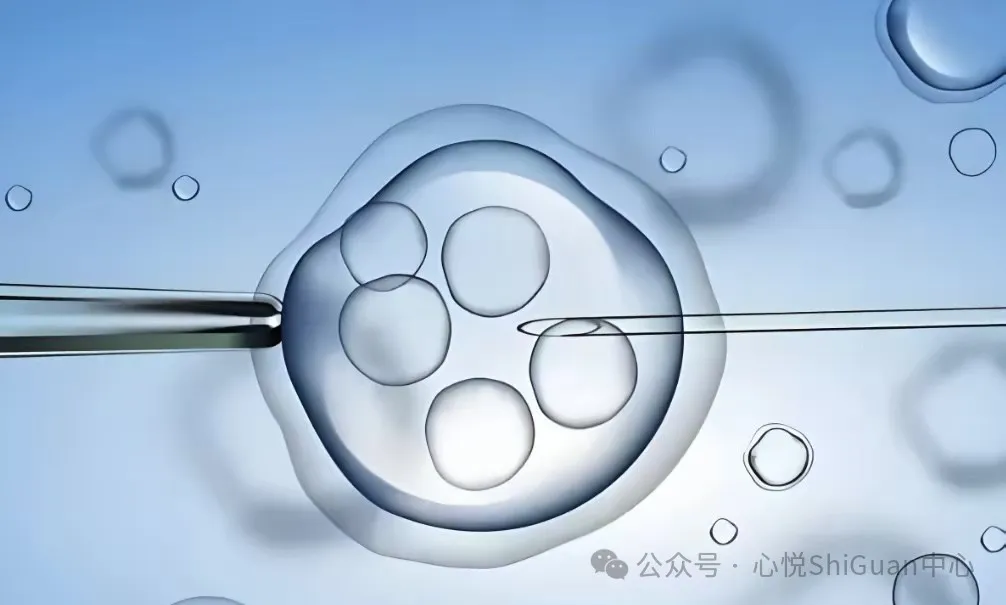

第三代试管婴儿:试管婴儿胚胎移植后,有哪些注意事项!